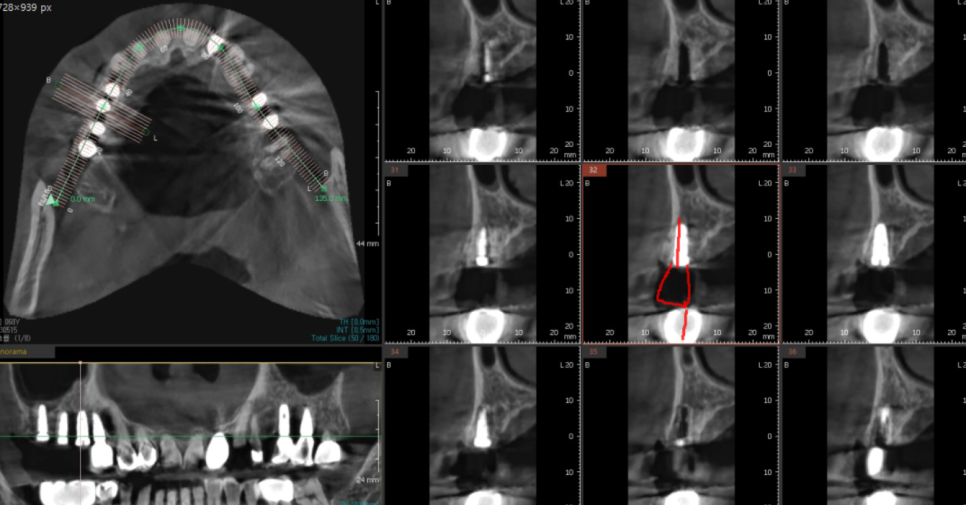

23.05.15

3d-ct를 통해

남아있는 뼈 분석하고 임플란트까지 완료했습니다.

예전에 치아가 빠지고 씌울 때는

2개 치아 -> 3개 머리 브릿지 형태로 하셨지만

20년만에 치료하시는만큼

더 튼튼하게 씹을 수 있도록

치아 개수대로 계획을 잡아드렸습니다.

3개 치아 빠진 개수만큼

고덕동 임플란트

진행해드렸습니다.